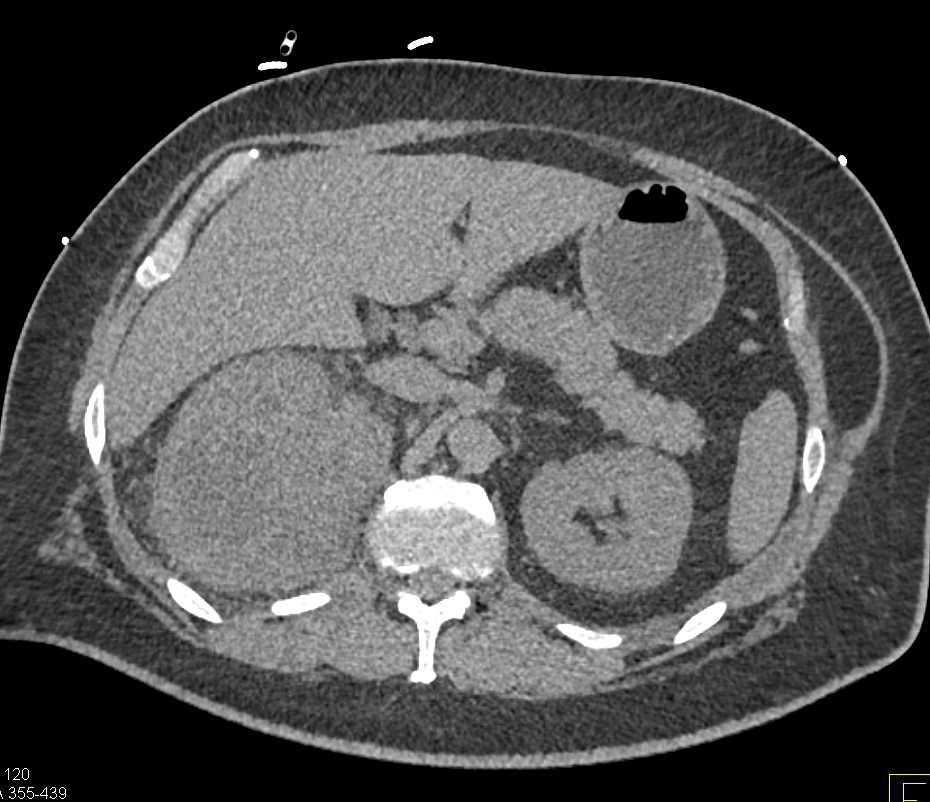

Bosniak 2F Cyst Left Kidney